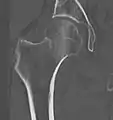

Typically, radiographs are taken of the hip from the front (AP view), and side (lateral view). Frog leg views are to be avoided, as they may cause severe pain and further displace the fracture.[5] In situations where a hip fracture is suspected but not obvious on x-ray, an MRI is the next test of choice. If an MRI is not available or the patient can not be placed into the scanner a CT may be used as a substitute. MRI sensitivity for radiographically occult fracture is greater than CT. Bone scan is another useful alternative however substantial drawbacks include decreased sensitivity, early false negative results and decreased conspicuity of findings due to age-related metabolic changes in the elderly.[16]

A case demonstrating a possible order of imaging in initially subtle findings:

X-ray showing a suspected compressive subcapital fracture as a radiodense line

CT scan shows the same, atypical for a fracture since the cortex is coherent

T1-weighted, turbo spin echo, MRI confirms a fracture, as the surrounding bone marrow has low signal from edema.